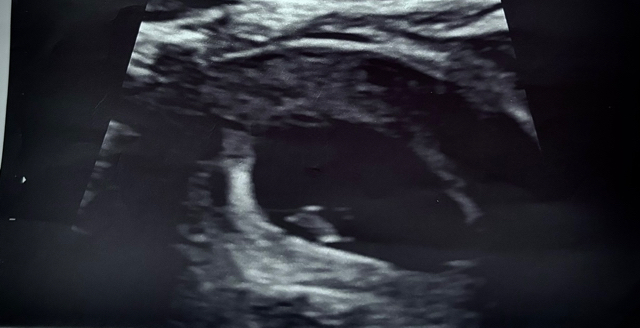

12 week scan!

Officially announced it publicly 😊🩷 due date has now changed to November 4th baby is measuring 3 days ahead

First scan 6+5

Second scan 9+1

Third scan 12